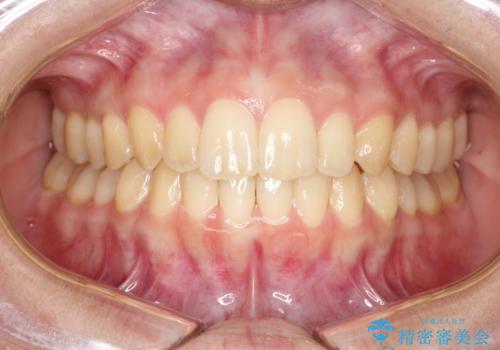

出ている前歯をインビザラインにて引っ込める

- 前歯が少し前に出ているのが気になるとのことで来院されました。

インビザラインにて上顎の歯を全体的に後方に移動させて前歯を引っ込める計画としました。

使用時間を守っていただけたので、比較的スムーズに矯正を終了することができました。